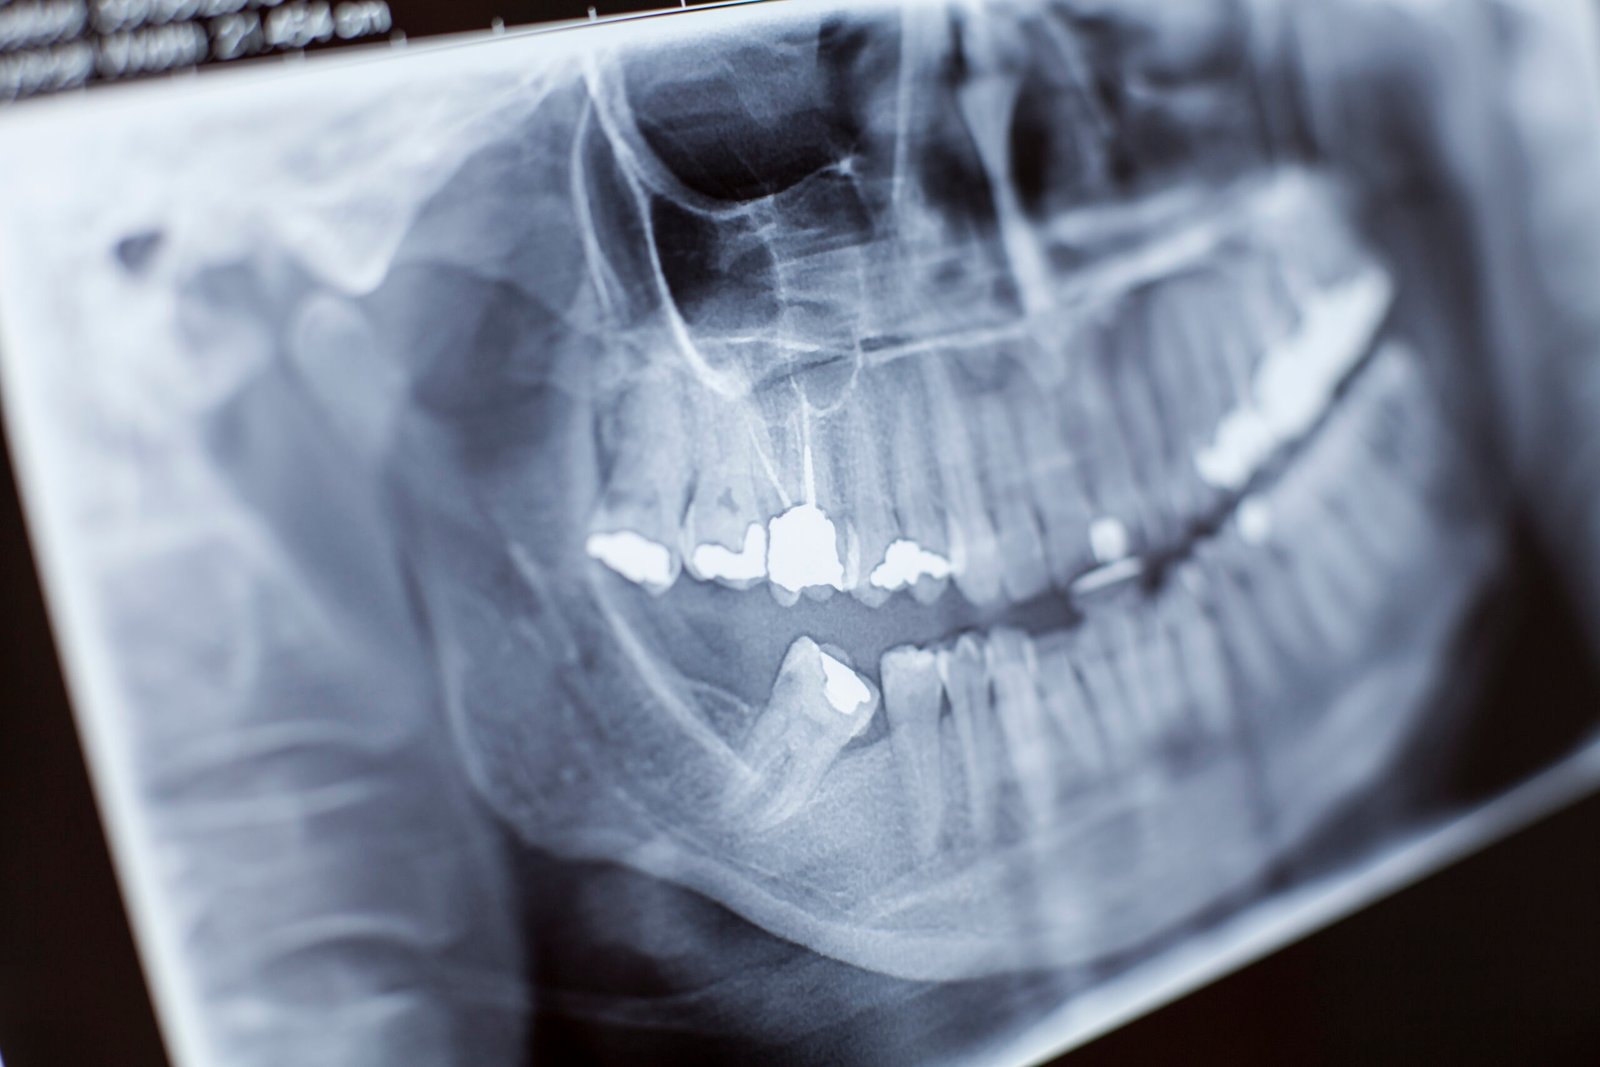

La radiografía dental permite ver lo que no se aprecia a simple vista: caries entre dientes, infecciones en la raíz, pérdida de hueso por enfermedad periodontal, posición real de las muelas del juicio o el hueso disponible para un implante. Por eso es una herramienta clave para diagnosticar con precisión y planificar tratamientos con seguridad.

• Panorámica: visión general de toda la boca (dientes, mandíbula, senos, cordales).